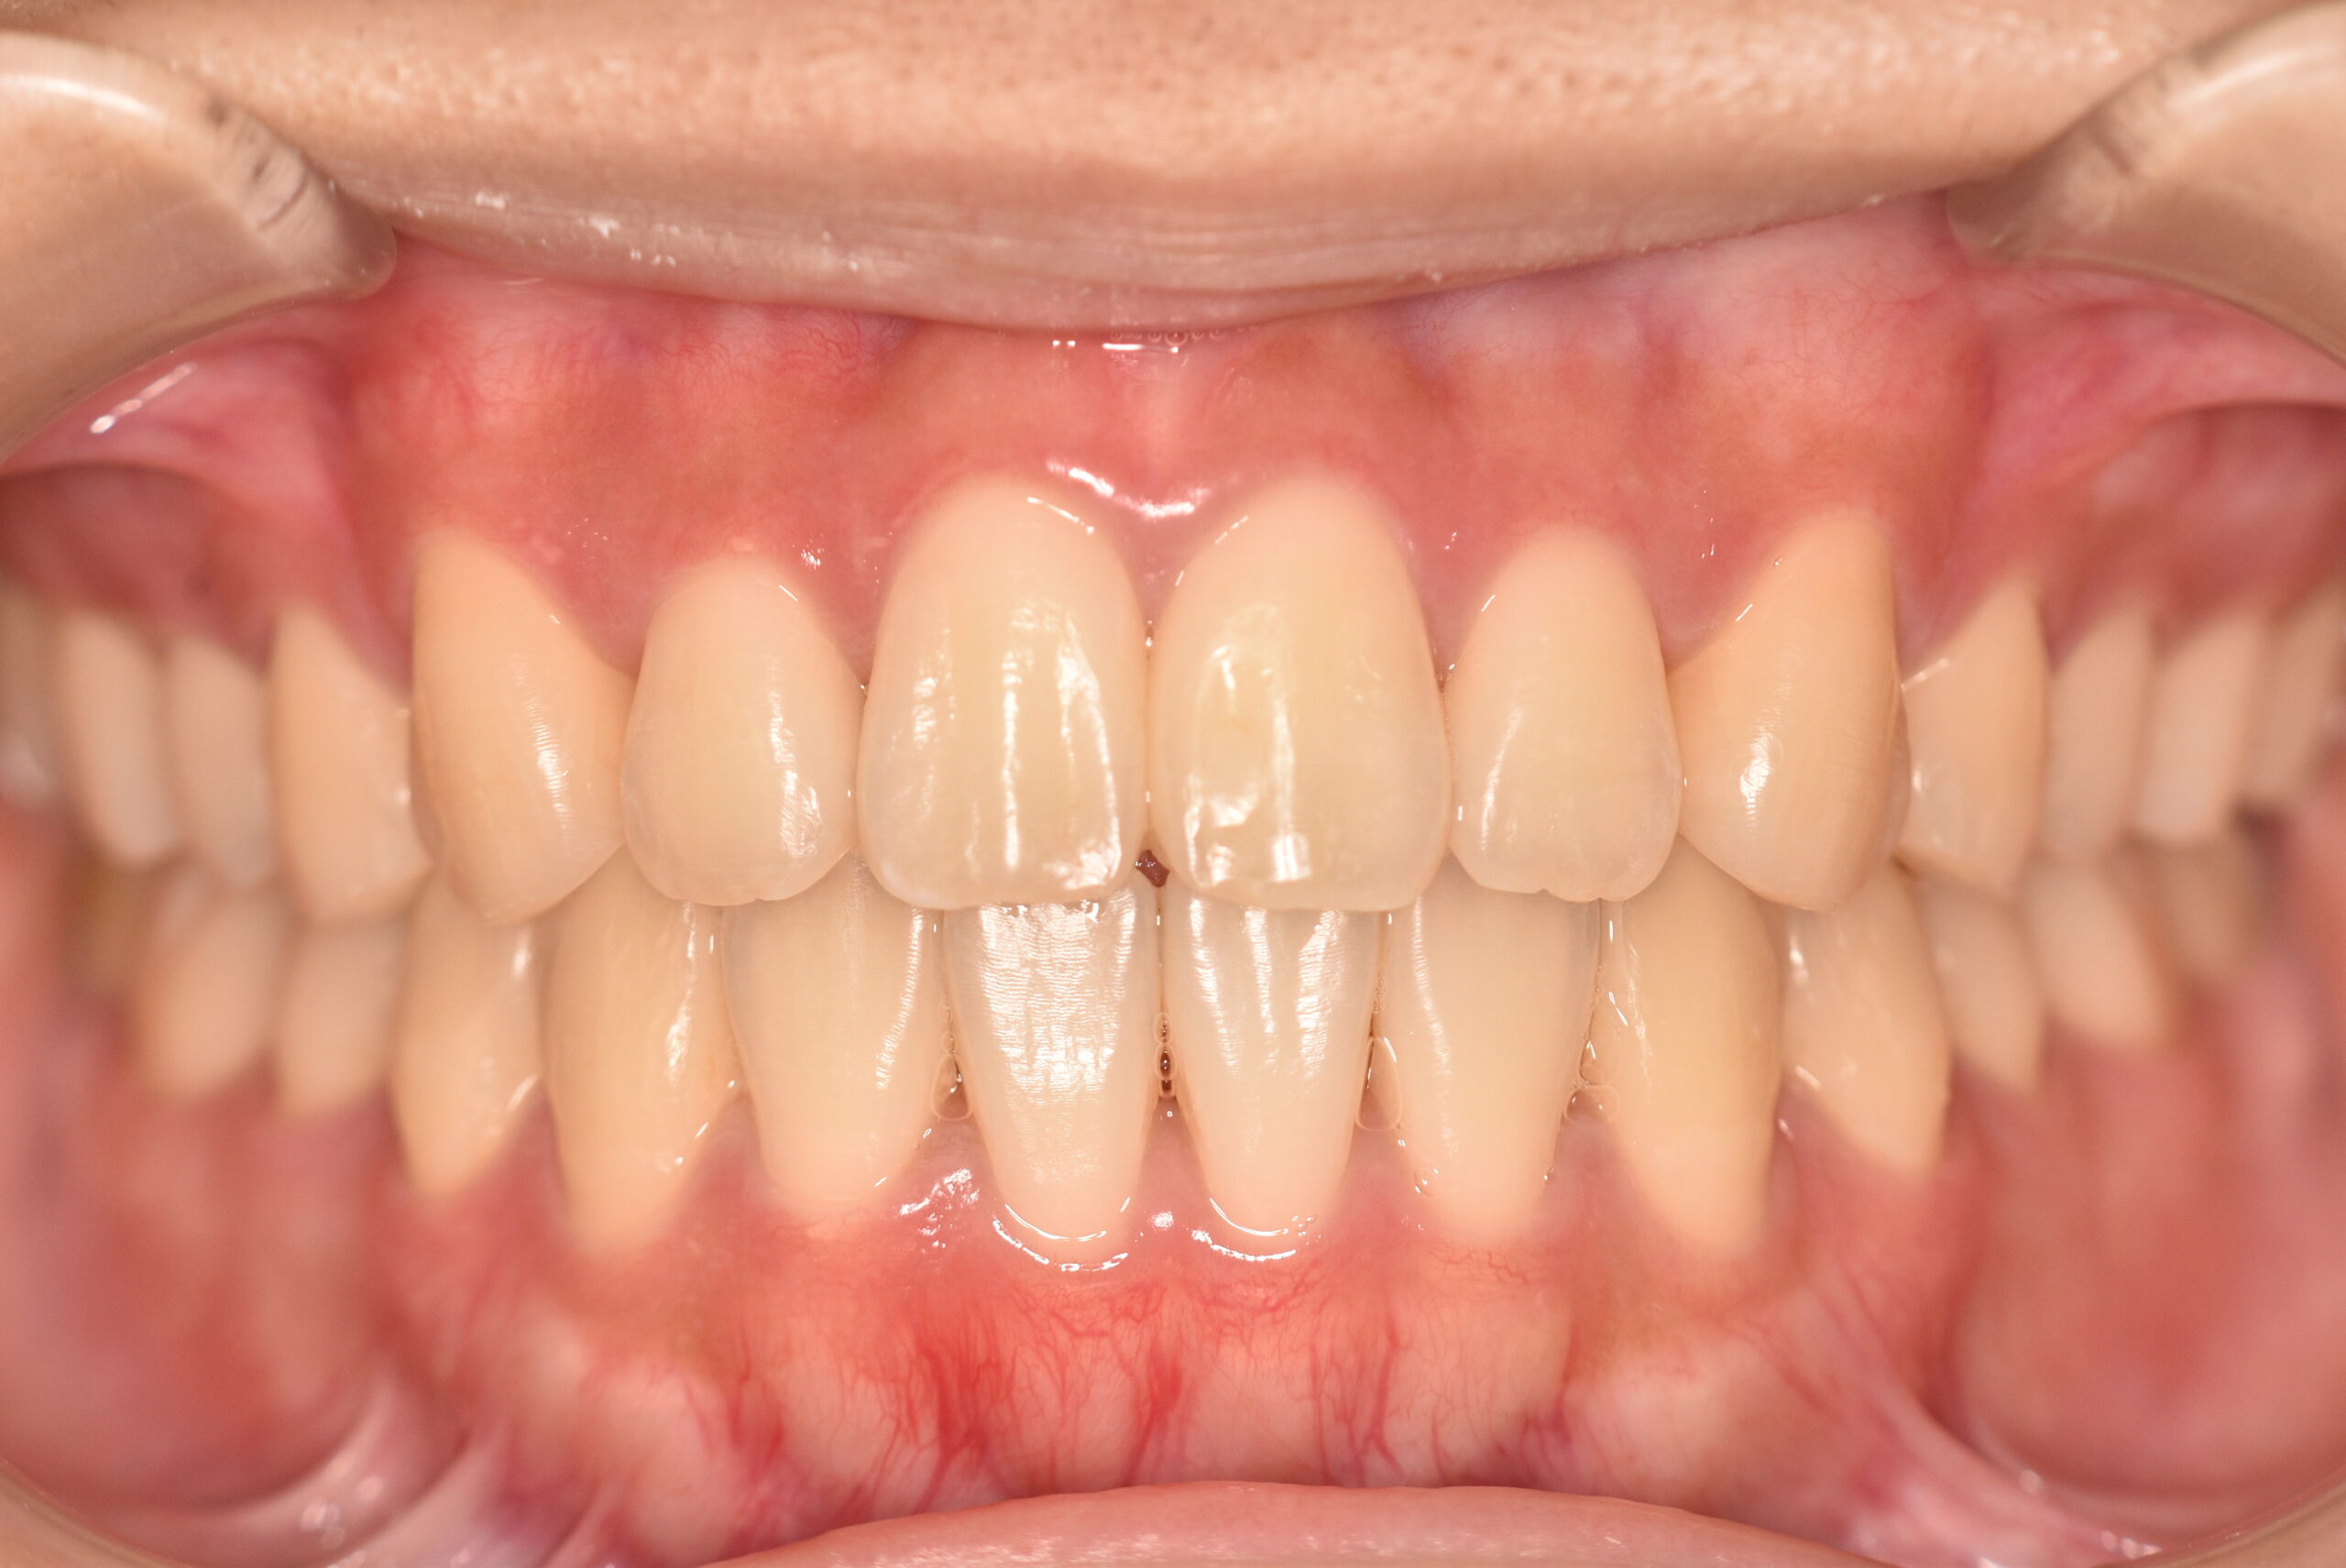

動的治療終了時

症例 症例 症例 症例 症例

治療内容の詳細 初診時17歳の女性で、かみ合わせが悪く少しガタガタしていることをを気にされ来院されました。

検査の結果、上下顎叢生を伴うアングル1級不正咬合と診断しました。

治療としては、非抜歯の上、マウスピース型矯正装置(インビザライン)で歯の配列を行いました。

治療期間は、1年10ヶ月でした。